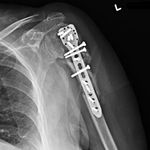

She was advised of the need to do some sort of stabilization which is necessary since the use of low-dose ultrasound has not helped in the healing process. She was unwilling to have any further operative intervention and sought further options. Eventually, she agreed to a fourth procedure of intra-medullary nail stabilization of the fracture and had this carried out in April 2011. An intramedullary nail was inserted in an antegrade manner and she has since gone on to heal the fracture site completely and has regained most of the function of the upper limb with no pain.

This case illustrates the possible complications that can occur with any surgery but also our commitment to our patients by sticking with them and making sure that a positive outcome is had despite the many challenges that may arise.